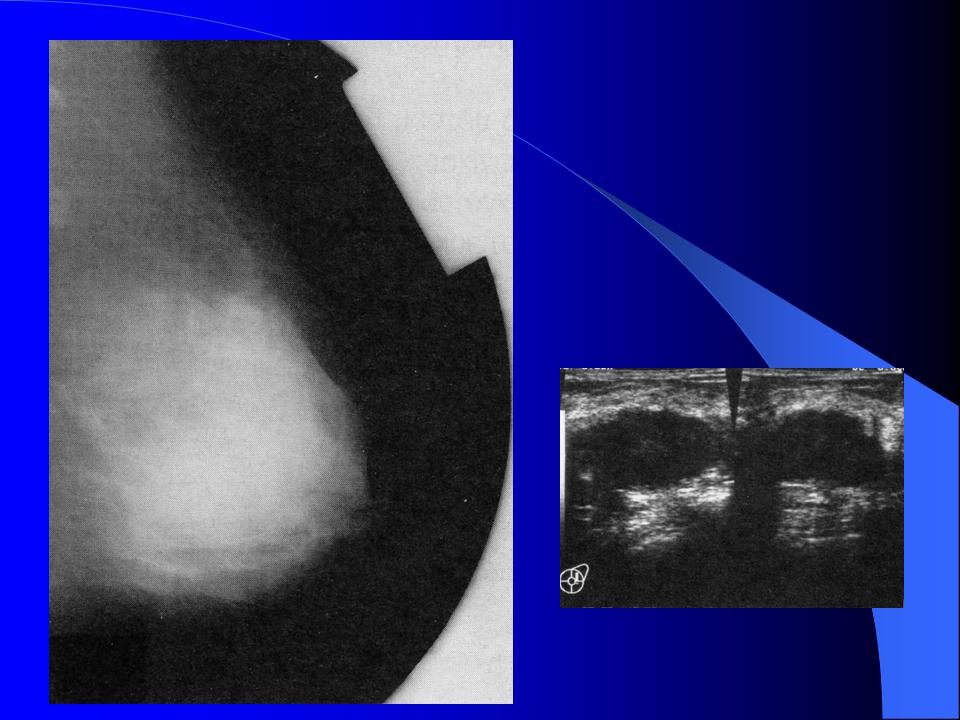

Χειρουργικές Παθήσεις Πάθηση Μάστου - ΚΑΛΟΗΘΕΙΣ ΠΑΘΗΣΕΙΣ ΜΑΣΤΟΥ ΣΥΓΓΕΝΕΙΣ ΑΝΩΜΑΛΙΕΣ ΤΩΝ ΜΑΣΤΩΝ - ΕΠΙΚΤΗΤΕΣ ΒΛΑΒΕΣ ΤΟΥ ΜΑΣΤΟΥ